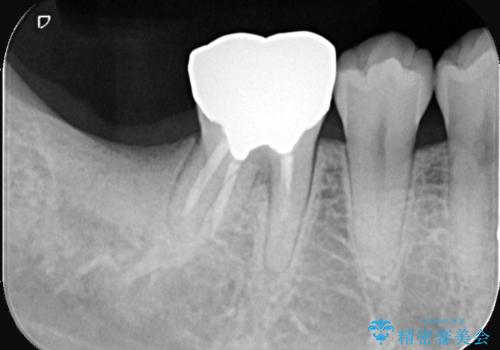

- 患者様は、奥歯を失ったことで「しっかり噛めるようになりたい」とのご希望で来院されました。ブリッジや入れ歯ではなく、インプラントによる治療を希望されたため、精密検査を実施。骨の状態が良好であったため、1回法(1回の手術でインプラント埋入とヒーリングアバットメント装着を同時に行う方法)を選択しました。これにより、外科的負担を軽減しながら、治療期間の短縮も図ることができました。

手術は1回で完了し、局所麻酔下でインプラントを埋入した後、ヒーリングアバットメントを装着。術後の腫れや痛みも少なく、患者様はスムーズに日常生活へ戻ることができました。約3ヶ月の治癒期間を経て、セラミッククラウンをセット。見た目の美しさはもちろん、天然歯に近い噛み心地を実現しました。患者様からは「違和感なくしっかり噛める」とご満足の声をいただきました。